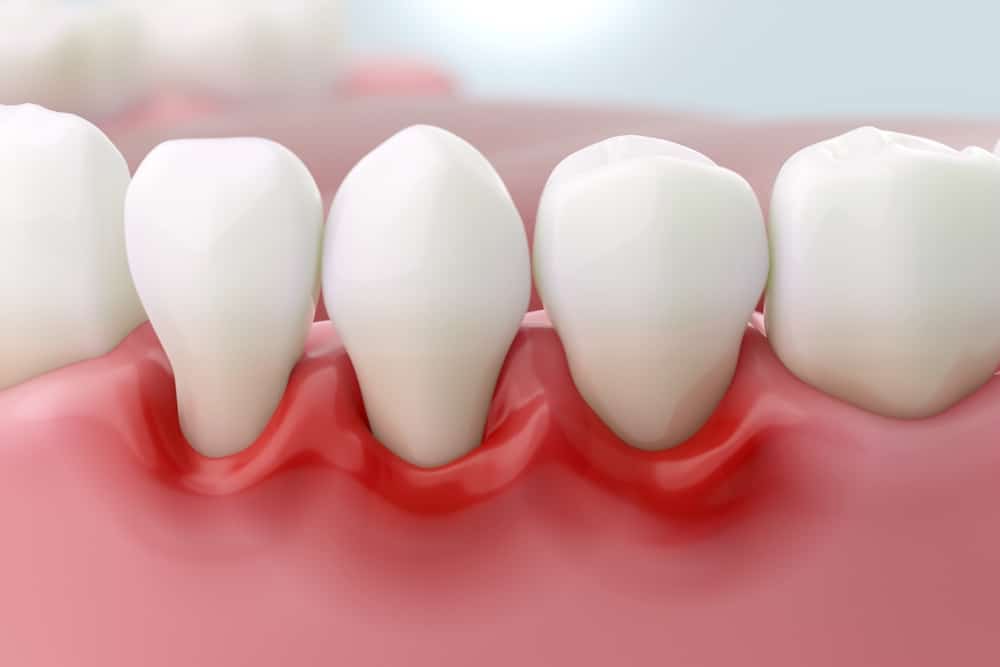

Gum Pain: Causes, Symptoms and Treatment Methods

Gum Pain: Causes, Symptoms and Treatment Methods 24 July 2025 Blog Gum Pain: Causes, Symptoms and Treatment Methods What is Gum Pain? Gum pain is a common oral and dental health problem that many people experience at some point in their lives and can directly impact their quality of life. While this pain can often […]